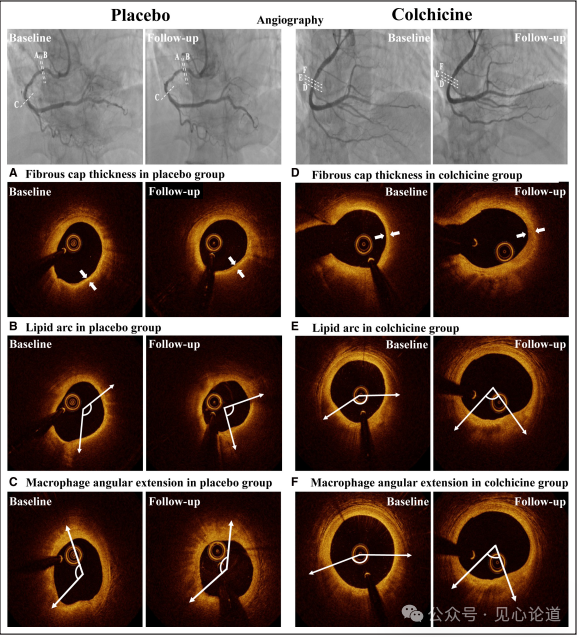

图2:冠状动脉斑块的代表性图片白色虚线表示目标病变。白色箭头之间的距离表示纤维帽厚度;白线为脂质弧和巨噬细胞角延伸。A,安慰剂组纤维帽厚度的代表性图片。B,安慰剂组脂质弧线的代表性图片。C,安慰剂组巨噬细胞角延伸的代表性图片。D,秋水仙碱组纤维帽厚度的代表性图片。E,秋水仙碱组脂质弧线代表图。F,秋水仙碱组巨噬细胞角延伸的代表性图片

图2显示了基线和12个月随访时患者的代表性OCT图像。与安慰剂组相比,秋水仙碱治疗显著影响了平均脂质弧度的变化和巨噬细胞的平均角度延伸。最小管腔面积在随访期间无明显变化。